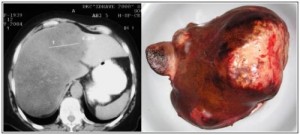

Какви са раковите тумори на черния дроб?Раковите (злокачествени)

тумори в черния дроб или са възникнали в черния дроб (първичен рак на черния дроб) или се разпространяват от други места по тялото (метастазирал рак на черния дроб). Повечето ракови тумори на черния дроб са метастатични.

Какво е хепатома (първичен рак на черния дроб)?Нарича се още и хепатоцелуларен карцином. Това е най-често срещаната форма на първичен рак на черния дроб. Хронична инфекция от хепатит В и С повишава риска от развитие на този вид рак. Други причини включват канцерогенни вещества, алкохолизъм и хронична чернодробна цироза.